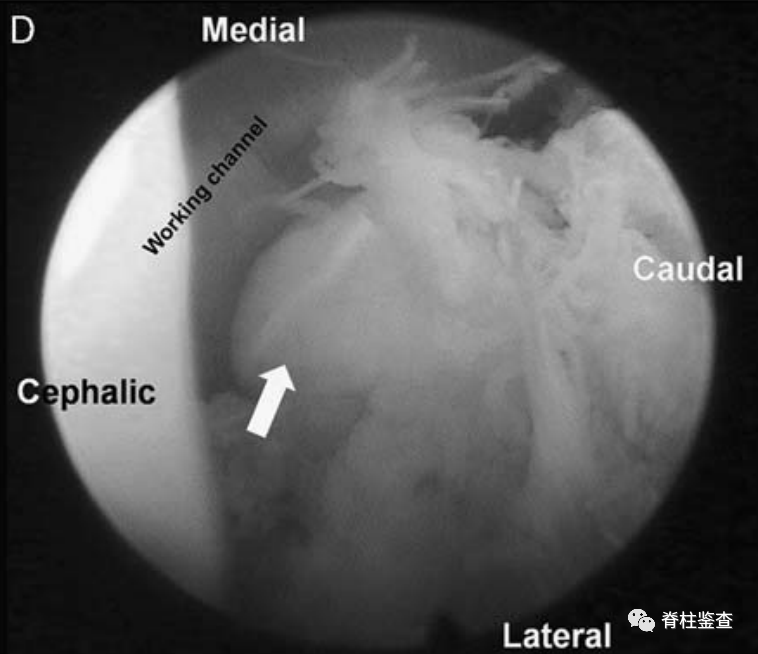

在瘢痕组织与内侧小关节的交界处剥离瘢痕组织(白色↓)。